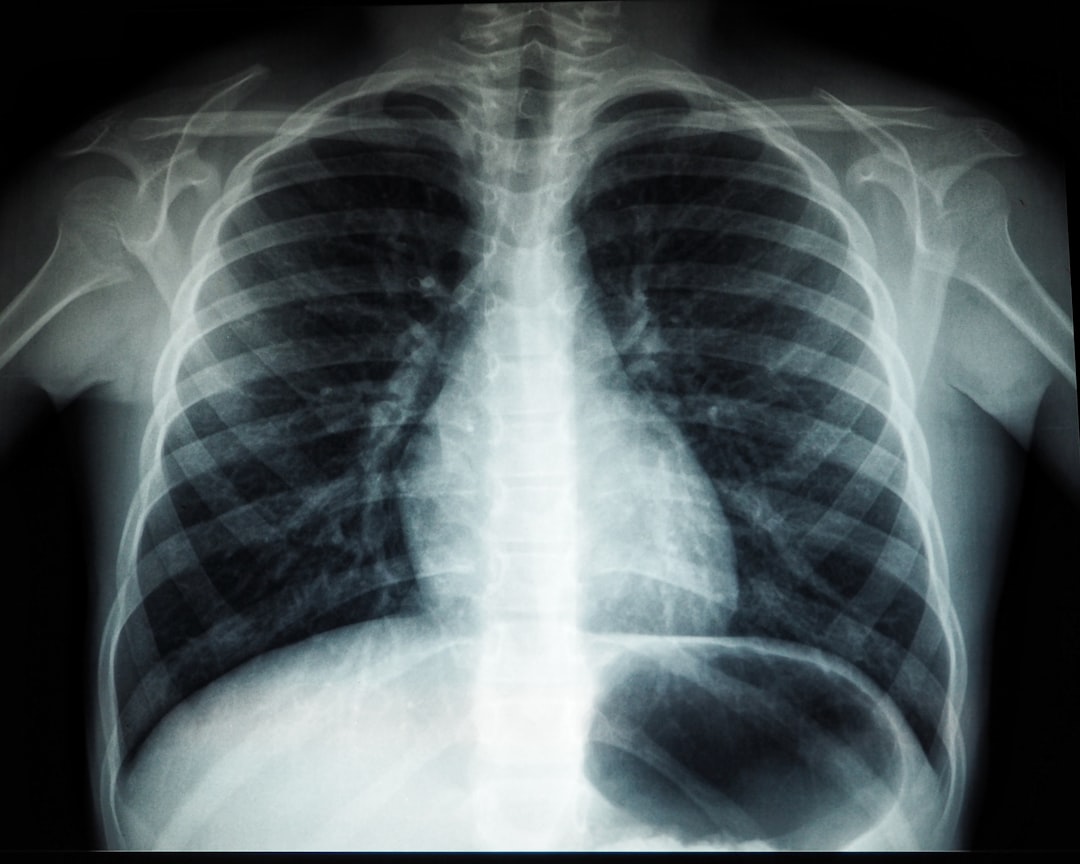

잠복결핵확인서를 발급받기 위해서는 먼저 검사를 받아야 합니다. 이 검사는 일반적으로 X선 촬영이나 PPD 피부반응 검사로 진행됩니다. 검사 후, 결과가 음성이면 보건소 또는 지정 병원에서 확인서를 요청할 수 있습니다. 필요한 서류로는 신분증과 검사 결과지 등이 있으며, 이들을 준비하면 신청 절차는 순조롭게 진행될 것입니다. 신고 당시 예약이 필요하거나 대기 시간이 있을 수 있으니 미리 시간을 고려하는 것이 좋습니다.